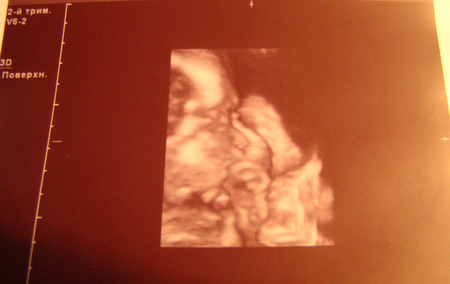

А вот и наша куколка. Сосет пальчик и даже не подозревает, что мама с папой чуть с ума не сошли из-за ее затишья

Какая-то она у нас большелобая ))) Ну видимо еще все не совсем сформировано ))) Здоровья тебе, моя девочка. Мы с папочкой тебя очень ждем

и больше нас не пугай